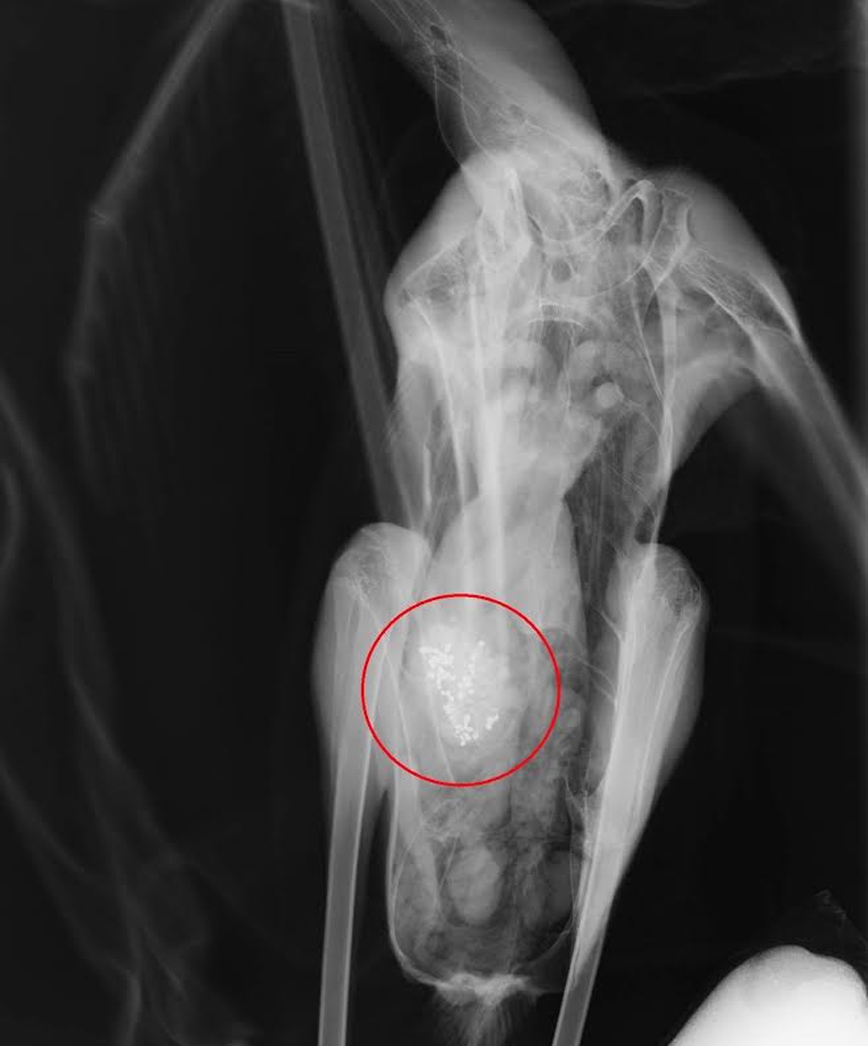

«Από τα τέλη Ιανουαρίου που παραλάβαμε τα δύο πρώτα φοινικόπτερα με συμπτώματα δηλητηρίασης, έως σήμερα έχουμε νοσηλεύσει στις εγκαταστάσεις μας συνολικά 9 πουλιά. Όλα τους είχαν καταπιεί σκάγια. Στην ακτινογραφία φαίνονται τα σκάγια στο στομάχι του πουλιού. Δεν είναι πυροβολημένο καθώς η νεκροψία έδειξε ότι τα είχε καταπιεί», σημείωσε στο Αθηναϊκό Πρακτορείο Ειδήσεων ο Σταύρος Καλπάκης από το σωματείο «Δράση για την άγρια ζωή».